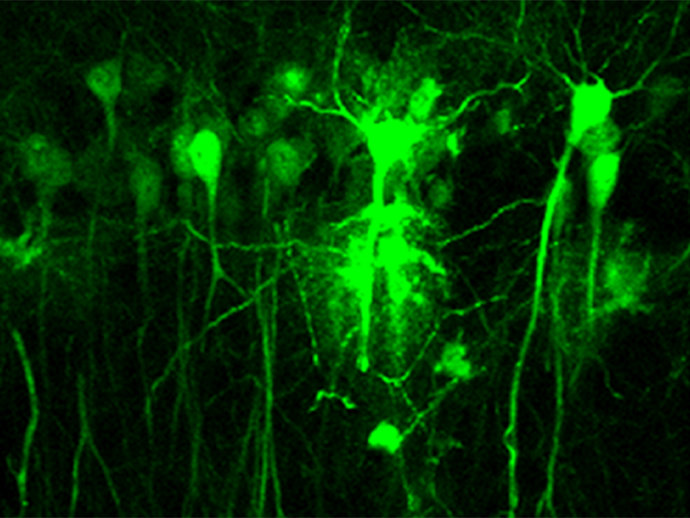

Neruonas - UPO

Un estudio liderado por investigadores del Consejo Superior de Investigaciones Científicas (CSIC) y el Centro Investigación Biomédica en Red Enfermedades Neurodegenerativas (Ciberned), en colaboración con la División de Neurociencias de la Universidad de Pablo Olavide (UPO), ha demostrado que es imprescindible la presencia del receptor dopaminérgico D2 en las neuronas del hipocampo para que la dopamina, uno de los principales neurotransmisores cerebrales, pueda modular los cambios sinápticos responsables de la adquisición y la consolidación de la memoria.

En la adquisición y la consolidación de la memoria está implicado el hipocampo mediante cambios plásticos en las sinapsis neuronales que almacenan la información recibida de otros núcleos y del exterior. "Hasta el momento se sabía que la dopamina era capaz de modular estos cambios, aunque se desconocían los mecanismos neuronales involucrados. En trabajos previos de laboratorio se había demostrado la importancia del receptor D1 en la memoria espacial y la plasticidad sináptica, pero quedaba por desvelar la implicación del receptor D2", señala Rosario Moratalla, investigadora del CSIC en el Instituto Cajal.

Combinando el uso de un modelo genético de ausencia del receptor D2 con estrategias de manipulación genética, los investigadores han comprobado que la falta de este receptor reduce la plasticidad sináptica en el hipocampo.